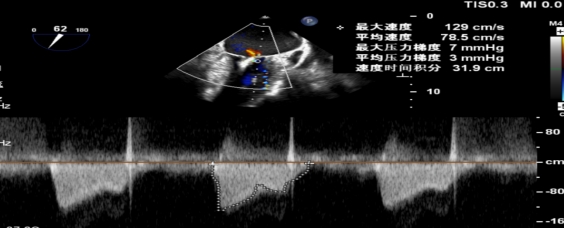

手术当日,在全身麻醉及TEE全程导航下,陈玺全副主任团队凭借丰富的临床经验与精湛操作技巧,顺利完成房间隔穿刺、瓣叶精准定位等关键步骤。针对患者二尖瓣A2/P2 区域反流靶点,团队精准夹合瓣叶,经X-plane技术与三维超声反复确认夹持质量后,成功释放一枚MitraClip XTR夹子。术后即时评估显示,患者二尖瓣反流由术前3 +重度降至轻度,平均跨瓣压仅3mmHg,手术达到预期效果,全程无并发症发生。

术后平均跨瓣压差3mmHg